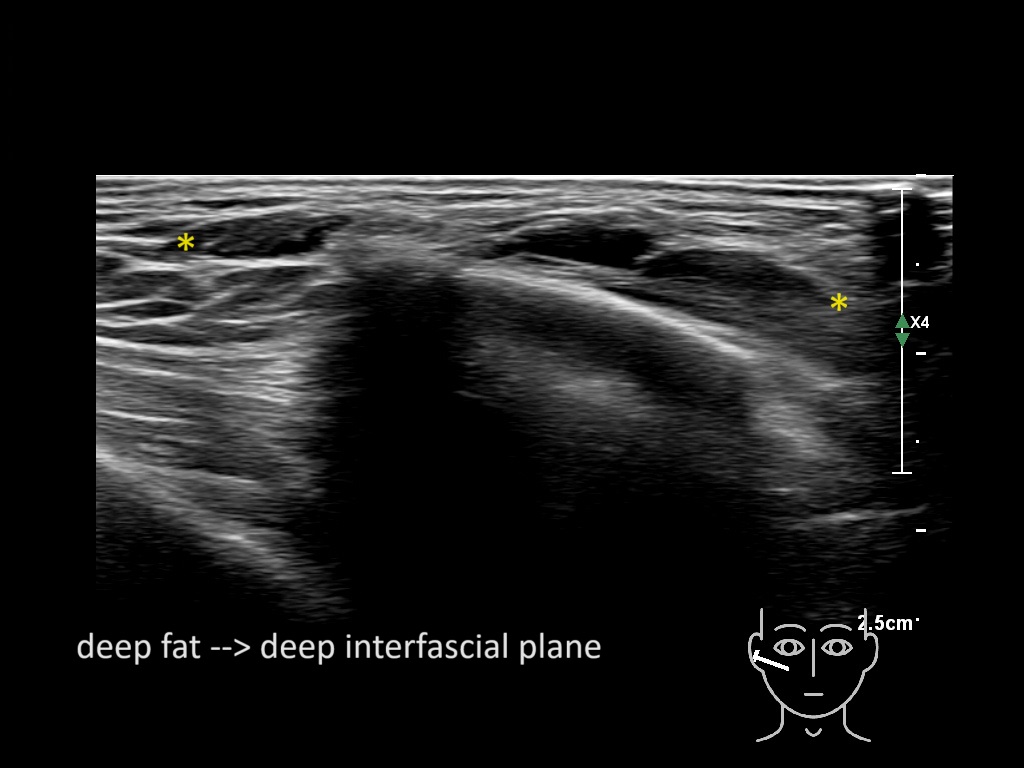

Filler behavior - Temple zygoma US

Study the first image to recognize the different layers. If you are sure about the layers, swipe to the second image to view the answer (if applicable).

Hover over an image to view the secondary image or click on the image title for more information.